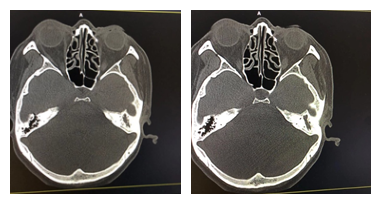

乳突CT提示:左侧中耳乳突炎